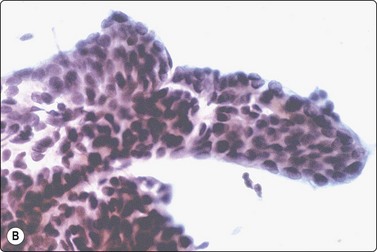

Papillary carcinoma (Figs 6.30-6.47)159-162

Papillary carcinoma (PC) is the most common type of thyroid cancer, occurring predominantly in females, in all age groups but most often in the third to fifth decades.42 It accounts for 90% of childhood thyroid malignancies. Five to ten percent of cases have had prior head and neck irradiation, usually in the first two decades of life. Most cases show clinically evident metastatic cervical lymphadenopathy at presentation, yet the prognosis is usually good, especially in children and young adults. RET/PTC rearrangements and BRAF mutation are often seen.159 PC is rarely encapsulated, infiltrates the thyroid in an irregular manner and is often multifocal with variable degrees of cystic change. Histological hallmarks of the tumor are the branching papillary structures with fibrovascular cores, lined by cuboidal or columnar cells with ‘ground-glass’ nuclei (‘Orphan Annie’ eyes). These cells show nuclear grooves and/or INCIs, and psammoma bodies are seen in many cases.

Page 135

Smears in PC are cellular with numerous three-dimensional and papillary fragments (Fig. 6.30) with or without vascular cores. Often, papillae not removed intact by the needle appear as flat sheets. Sheets of cells show a distinct anatomical border, formed by a row of cuboidal or columnar cells (Fig 6.31A) with focal nuclear crowding and overlapping, features that distinguish sheets of PC from those representing benign macrofollicles (Fig. 6.31B). The tip of a papilla may be seen as a finger-like aggregate of cells with a similar edge (Figs 6.32 and 6.33A). Naked true papillary connective tissue cores are sometimes found and can be diagnostically helpful. Trabecular fragments (Fig. 6.33B) (also present in FN) are represented in smears by cohesive finger-like structures and must not be mistaken for papillae. Seventeen percent of cases show concentrically organized aggregates of tumor cells or ‘swirls’ (Fig. 6.34), the most peripherally located cells appearing ovoid with nuclei oriented perpendicular to the radius of the swirl.163 A few cases show only dispersed single cells and syncytial aggregates; diagnosis then relies on identification of nuclear features of PC.

image

Fig. 6.30 Papillary carcinoma

True papillary fragment with a vascular core; columnar cells with oval pale nuclei; intranuclear vacuoles, upper left (MGG, IP).

image image

Fig. 6.31 Comparison of sheets of papillary carcinoma and of macrofollicle in nodular goiter

(A) Papillary carcinoma. Flat sheet of epithelial cells; partly monolayered, partly with nuclear overlapping; uniformly enlarged, oval nuclei with pale powdery chromatin and small nucleoli; note ‘anatomical’ edge of a row of cells along upper edge (Pap, HP); (B) Nodular goiter. Flat monolayered sheet of cells from a disrupted macrofollicle; note frayed edges and uniformly small round nuclei (Pap, HP).

Fig. 6.32 Papillary carcinoma

Finger-like papillae with ‘anatomical’ edges (Pap, IP).

image image image